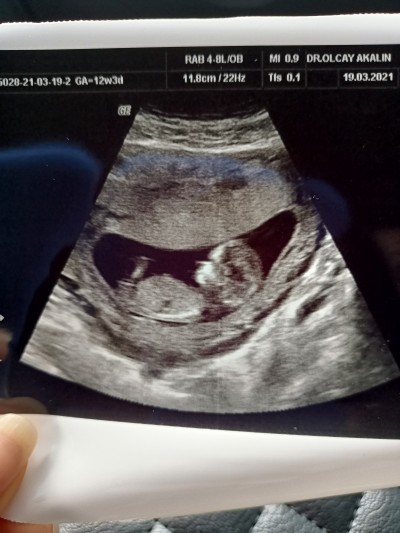

21 Mart 2021 Hamilelik Dönemi Genel kategorisinde (9 puan) sordu

erkek hissediyorum ama cinsiyet tahmini yapicak arkadaşlar varsa çok sevinirim

Gebelik haftası 12+3

Kapatılma nedeni: Cinsiyet tahminlerini sol üst köşeden konu dışı sohbetten sorabilirsiniz

Kese fasulye erkek gibi derler ama cıkıntı göremedim :) hayırlısı olsun gönlünüze göre versin inşallah

Erkek Çünkü Benim erkeklerde böyle duruyordu Şimdi Kızım olucak inşallah kendini Topluyo Poposunu Dönüyor erkek çocukları Erken gösterir kendini Ben 12 Co haftada öğrendim İmkanın varsa  iybir Özel hastaneye git Öğrenirsin Ama erkek Öğrendiğinde Msj at :)